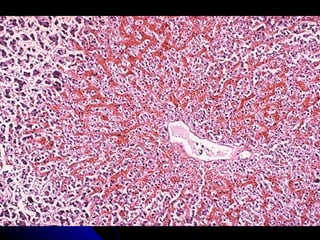

    Le foie : nécrose hépatocytaire centrolobulaire,

dilatation sinusoïdale.

Foie cardiaque

insuffisance cardiaque droite

hyperpression dans oreillette droite

congestion dans le domaine des veines sus-

hépatiques.

FOIE MUSCADE

Dilatation des veines, alternance de zones

rouge sombre et plus claires (foie "muscade").

Nécrose centrolobulaire

partiellement

hémorragique,

systématisée autour

des veines dilatées (V),

avec respect des zones

périportales . Espace

porte (EP).

Dilatation des veines,alternance de zones rouge sombre et plus claires (foie "muscade").

Nécrose centrolobulaire partiellement hémorragique, systématisée autour desveines dilatées (V), avec respect des zones périportales . Espace porte (EP).